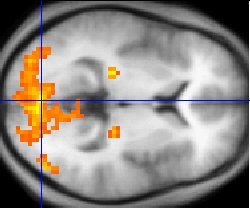

fMRI:顾名思义,是要研究针对某个脑活动(脑功能定位)激发某个脑区活动进行研究。这一项大幅提升MRI技术的创始人是日本科学家 小川诚二,他突破性使用血氧浓度相依对比(Blood oxygen-level dependent, BOLD)。简单而言就是,在某个脑区剧烈活动时候必然消耗更多的能量,自然就要消耗更多氧气(相对应的,PET技术针对能量代谢的成像技术,不过需要服用同位素药物),所以说通过检测血氧对比程度可以发现脑区活动情况。如下图,科学家可以通过BOLD探究脑部活动区别。